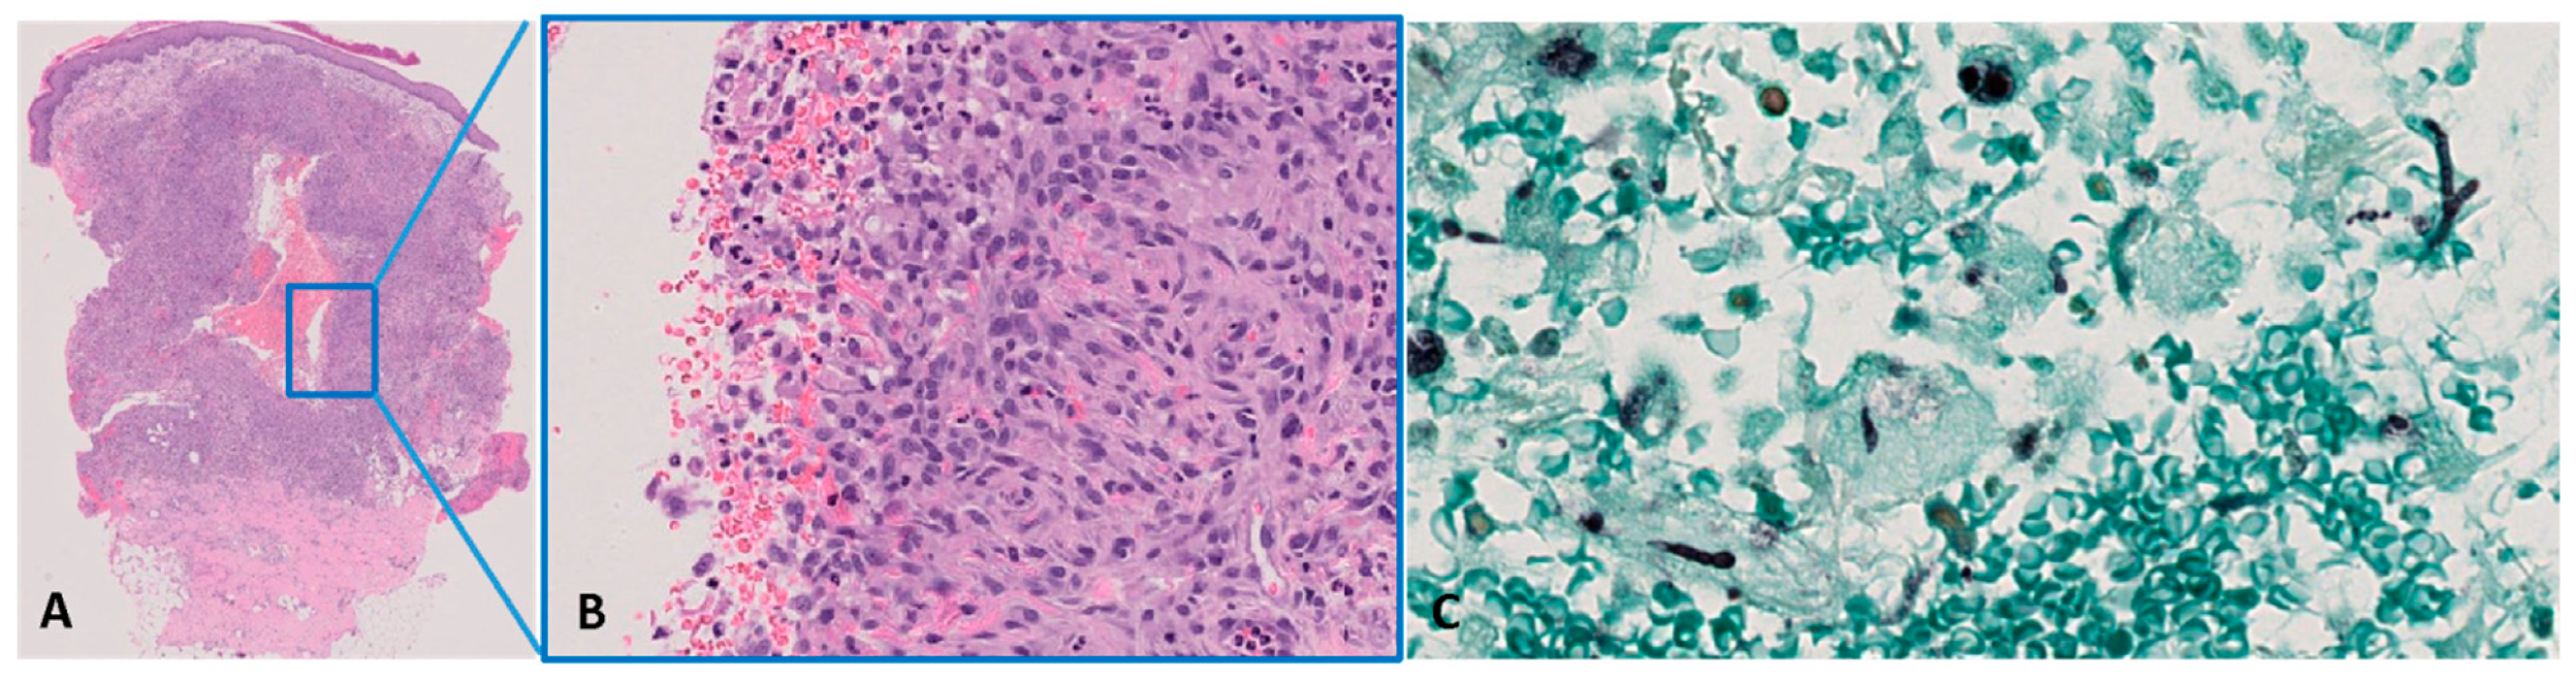

3. Case Report